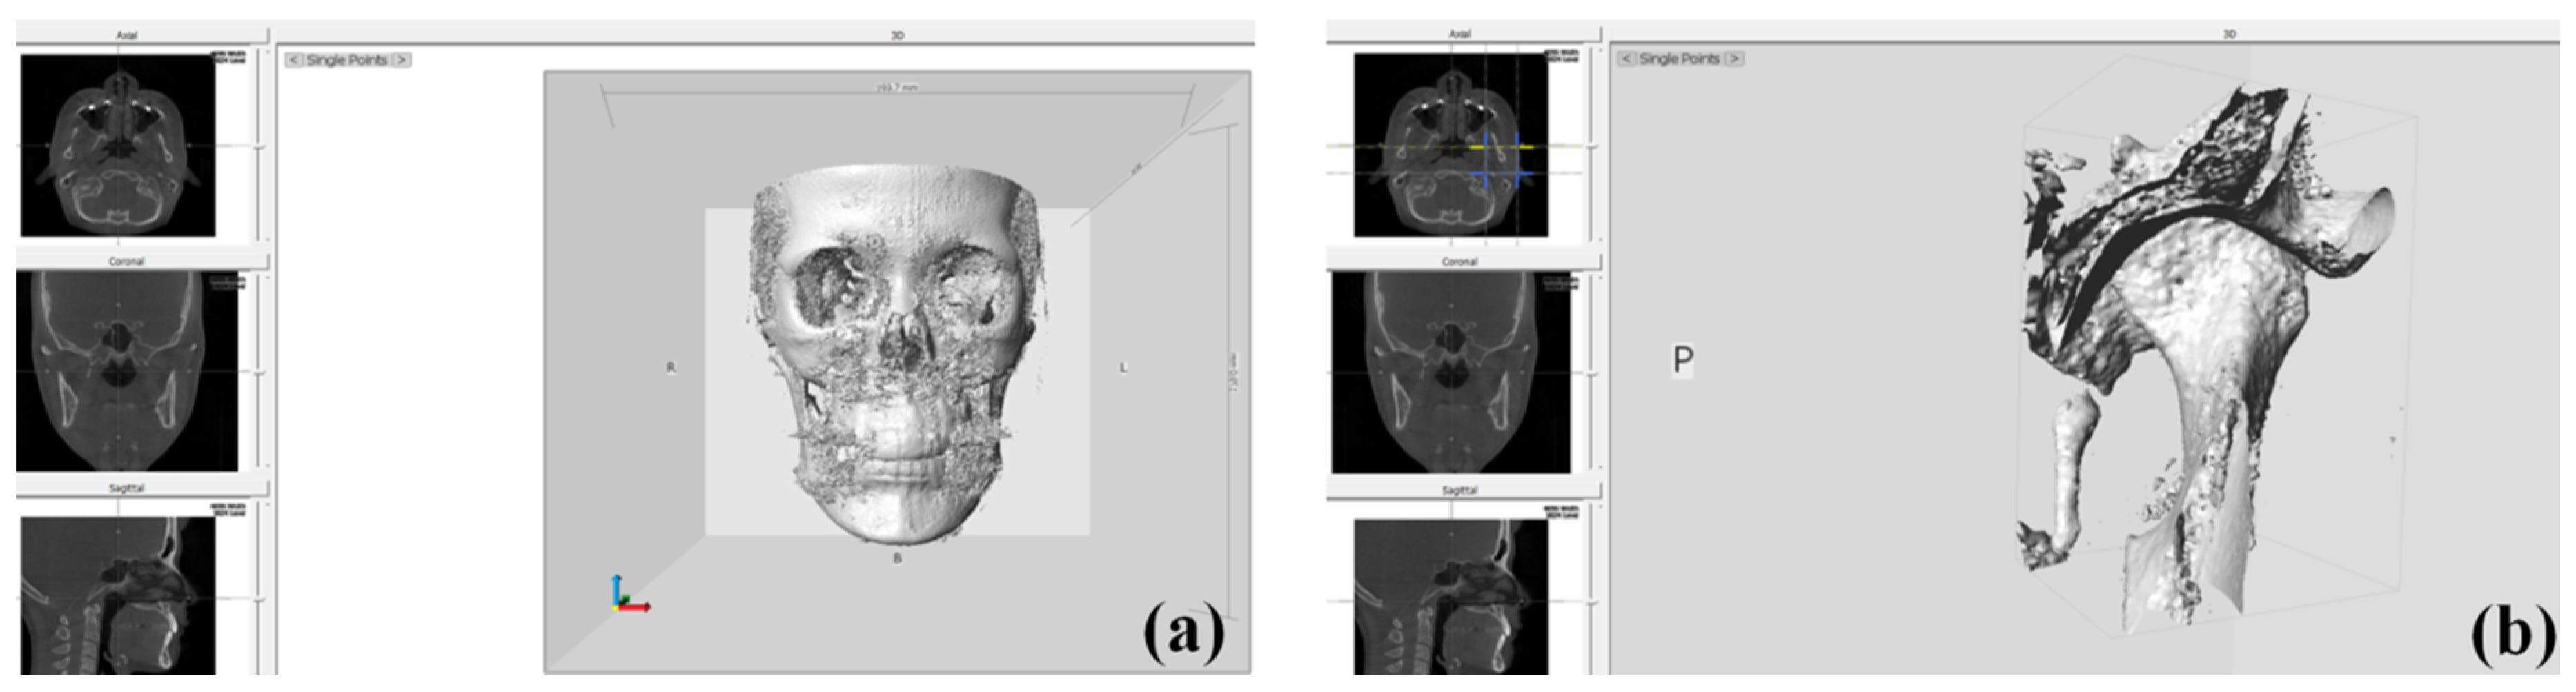

2.3. Condylar Volume Rendering